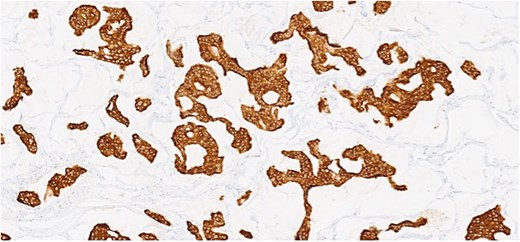

Herein, we present a 75-year-old man who, having been referred to our service with an inguinal hernia, raised concern about a palpable mass present in his right axilla. The main differential on initial examination was that of a simple epidermoid cyst, and consent was obtained for its removal during his elective hernia repair. Subsequent histology however, revealed a well differentiated MAC. There was extensive involvement of the deep and superficial reticular dermis (Figs 1and 2). Lymphovascular invasion was present. Sweat glands were focally involved by the carcinoma. The differential diagnosis included PCMC and metastasis from other primary sites of MAC such as breast, lung and gastrointestinal. Immunohistochemical profiling was performed on the specimen. CK 7, HER2 (4B5, 3+), GATA3 (strong, diffuse), and P16 (focal, weak) were positive (Figs 3–6). SOX10, CK 20, CDX2, TTF-1, p40, ER, and PR were negative which supported the diagnosis of MAC with either breast or PCMC origin based particularly on GATA3 expression.